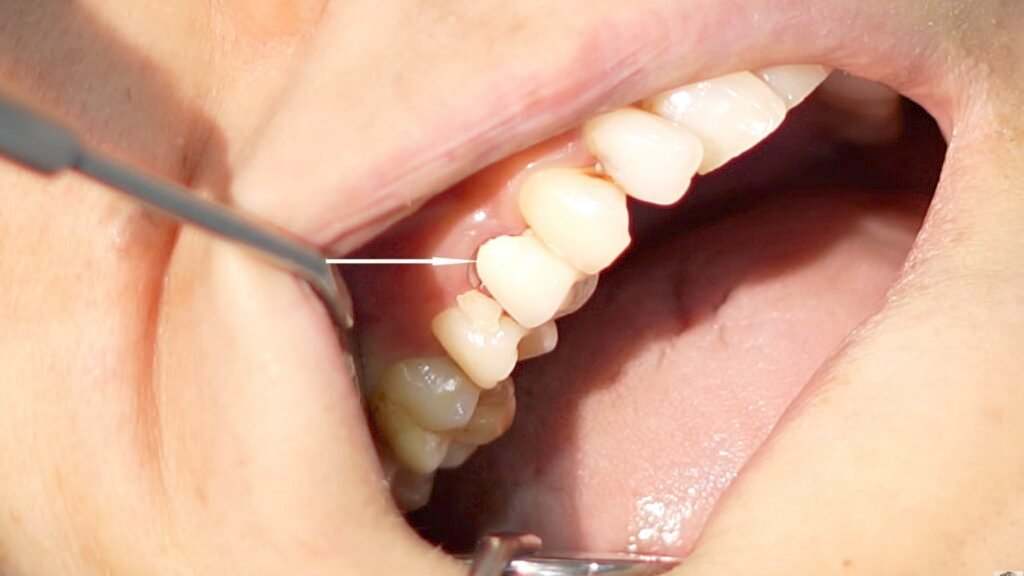

A patient presented with persistent and escalating pain one week following a root canal treatment and crown placement on a premolar tooth. Despite continuous intake of antibiotics and painkillers, the patient reported that the pain intensity was higher than before the initial procedure, significantly affecting her quality of life.

Upon examination, it was noted that the crown was improperly placed with faulty cementation; however, this was unlikely the primary cause of the severe pain. Radiographic analysis revealed a critical oversight during the initial root canal treatment: the premolar tooth had two root canals, but only one canal was partially filled, and the second canal was completely untreated. The filled canal was only obturated halfway, leaving the apical portion unsealed, which is a common source of persistent infection and pain.

The crown was removed using high-speed carbide burs, and the old filling was cleared. Both canals were thoroughly cleaned and filled to the apex, followed by composite buildup. The patient was recalled after three days for new crown placement and reported complete pain relief, no longer requiring any medication.